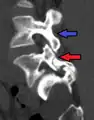

Anterolistesis L5/S1

Anterolistesis L5/S1. Flecha azul pars interarticularis normal. La flecha roja es una ruptura en pars interarticularis